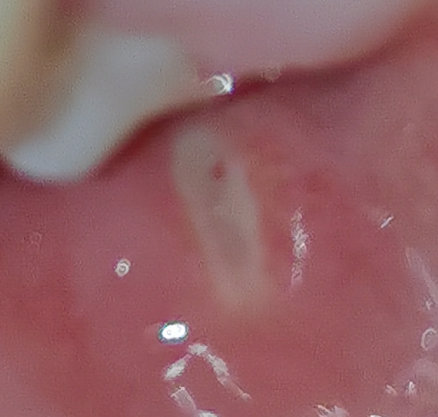

P.S. Временами (редко) десны чешутся в этих местах...на фотографии видно небольшие покраснения.

Прикрепленые фото